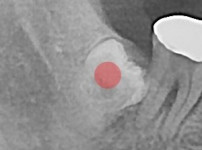

严重龋坏的智齿